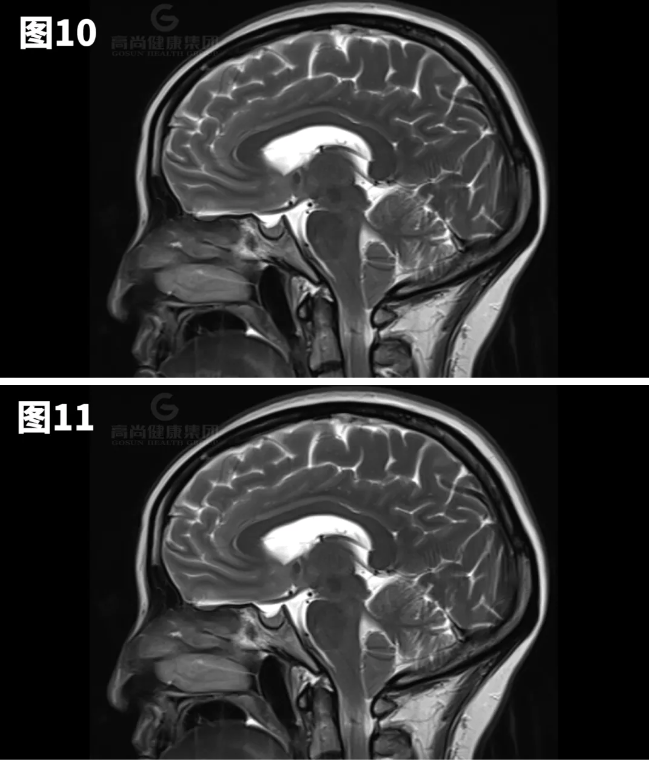

图8-11示小脑扁桃体向下疝出约7mm。

矢状位:扁桃体延伸到枕骨大孔下方,脑干压迫斜坡。

横断位:移位的扁桃体导致周围脑脊液闭塞、髓质前移以及脊髓动脉和椎动脉受压。